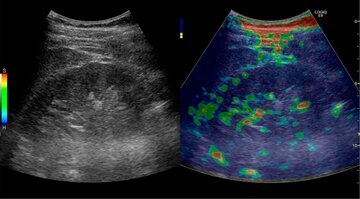

Традиционно для лечения хронического гепатита С применяется стандартная комбинированная терапия пегилированным интерфероном и рибавирином. Однако недавно появился новейший ингибитор вирусной протеазы, способный, являясь третьим компонентом в противовирусной терапии хронического гепатита С генотипа 1, значительно повысить ее эффективность даже у самых сложных групп пациентов.

В ходе симпозиума гепатологи выделили категории пациентов, которым целесообразно назначение тройной терапии: это пациенты с генотипом 1 вируса, с неудачей предшествующей терапии ХГС, со стадиями фиброза F3/F4 по METAVIR, с генотипом СТ или ТТгена IL28, лица негроидной расы, а также пациенты с сопутствующей ВИЧ-инфекцией.

В рамках симпозиума специалист по заболеваниям печени, старший научный сотрудник клиники пропедевтики внутренних болезней Первого МГМУ имени И. М. Сеченова, д. м.н. Алексей Буеверов центра, к. м.н. Павел Богомолов провели дискуссию "Двойная или тройная терапия хронического гепатита С: классика или современность?". Спикеры обсудили преимущества и недостатки каждого из способов лечения и сошлись на том, что для пациентов с неблагоприятным прогнозом терапии необходимо выбирать максимально эффективный третий агент. Его добавление к стандартной терапии может существенно повысить частоту устойчивого вирусологического ответа в сравнении со стандартной терапией у пациентов с предшествующей неудачей терапии. "Тройная терапия также демонстрирует высокую эффективность у пациентов с факторами плохого ответа на стандартное противовирусное лечение — выраженным фиброзом/циррозом печени, отсутствием снижения вирусной нагрузки в процессе первого курса, ТТ-генотипом интерлейкина-28В", - отметил А.О. Буеверов.

Профессор кафедры госпитальной терапии №2 лечебного факультета РНИМУ им. Н. И. Пирогова Минздрава России, член экспертной комиссии Совета Федерации России по здравоохранению, д. м.н. Игорь Никитин рассказал, чем нужно руководствоваться и на какие факторы обращать внимание при выборе третьего агента, а также при каких условиях следует назначать тройную терапию. "Появление новых молекул, безусловно, дает нам новые перспективы в лечении хронического гепатита С. При этом, я считаю, что тройная терапия необходима пациенту тогда, когда мы наблюдаем сложный клинический случай. Данные исследований говорят о том, что третий агент существенно повышает частоту достижения устойчивого вирусологического ответа у пациентов, ранее не отвечавших на двойную терапию, то есть у тех, у кого до сих пор не было шанса на излечение. Также важна эффективность в группе пациентов с фиброзом F3/F. То же касается и пациентов с коинфекцией ВИЧ — здесь третий агент даже может усилить эффект антиретровирусной терапии", — комментирует И.Г. Никитин.